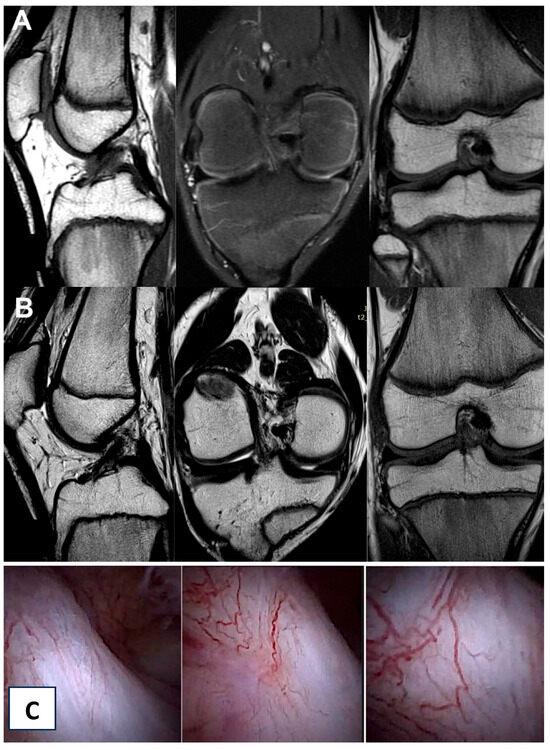

2.4. Imaging Examination

3.3. Imaging Analysis